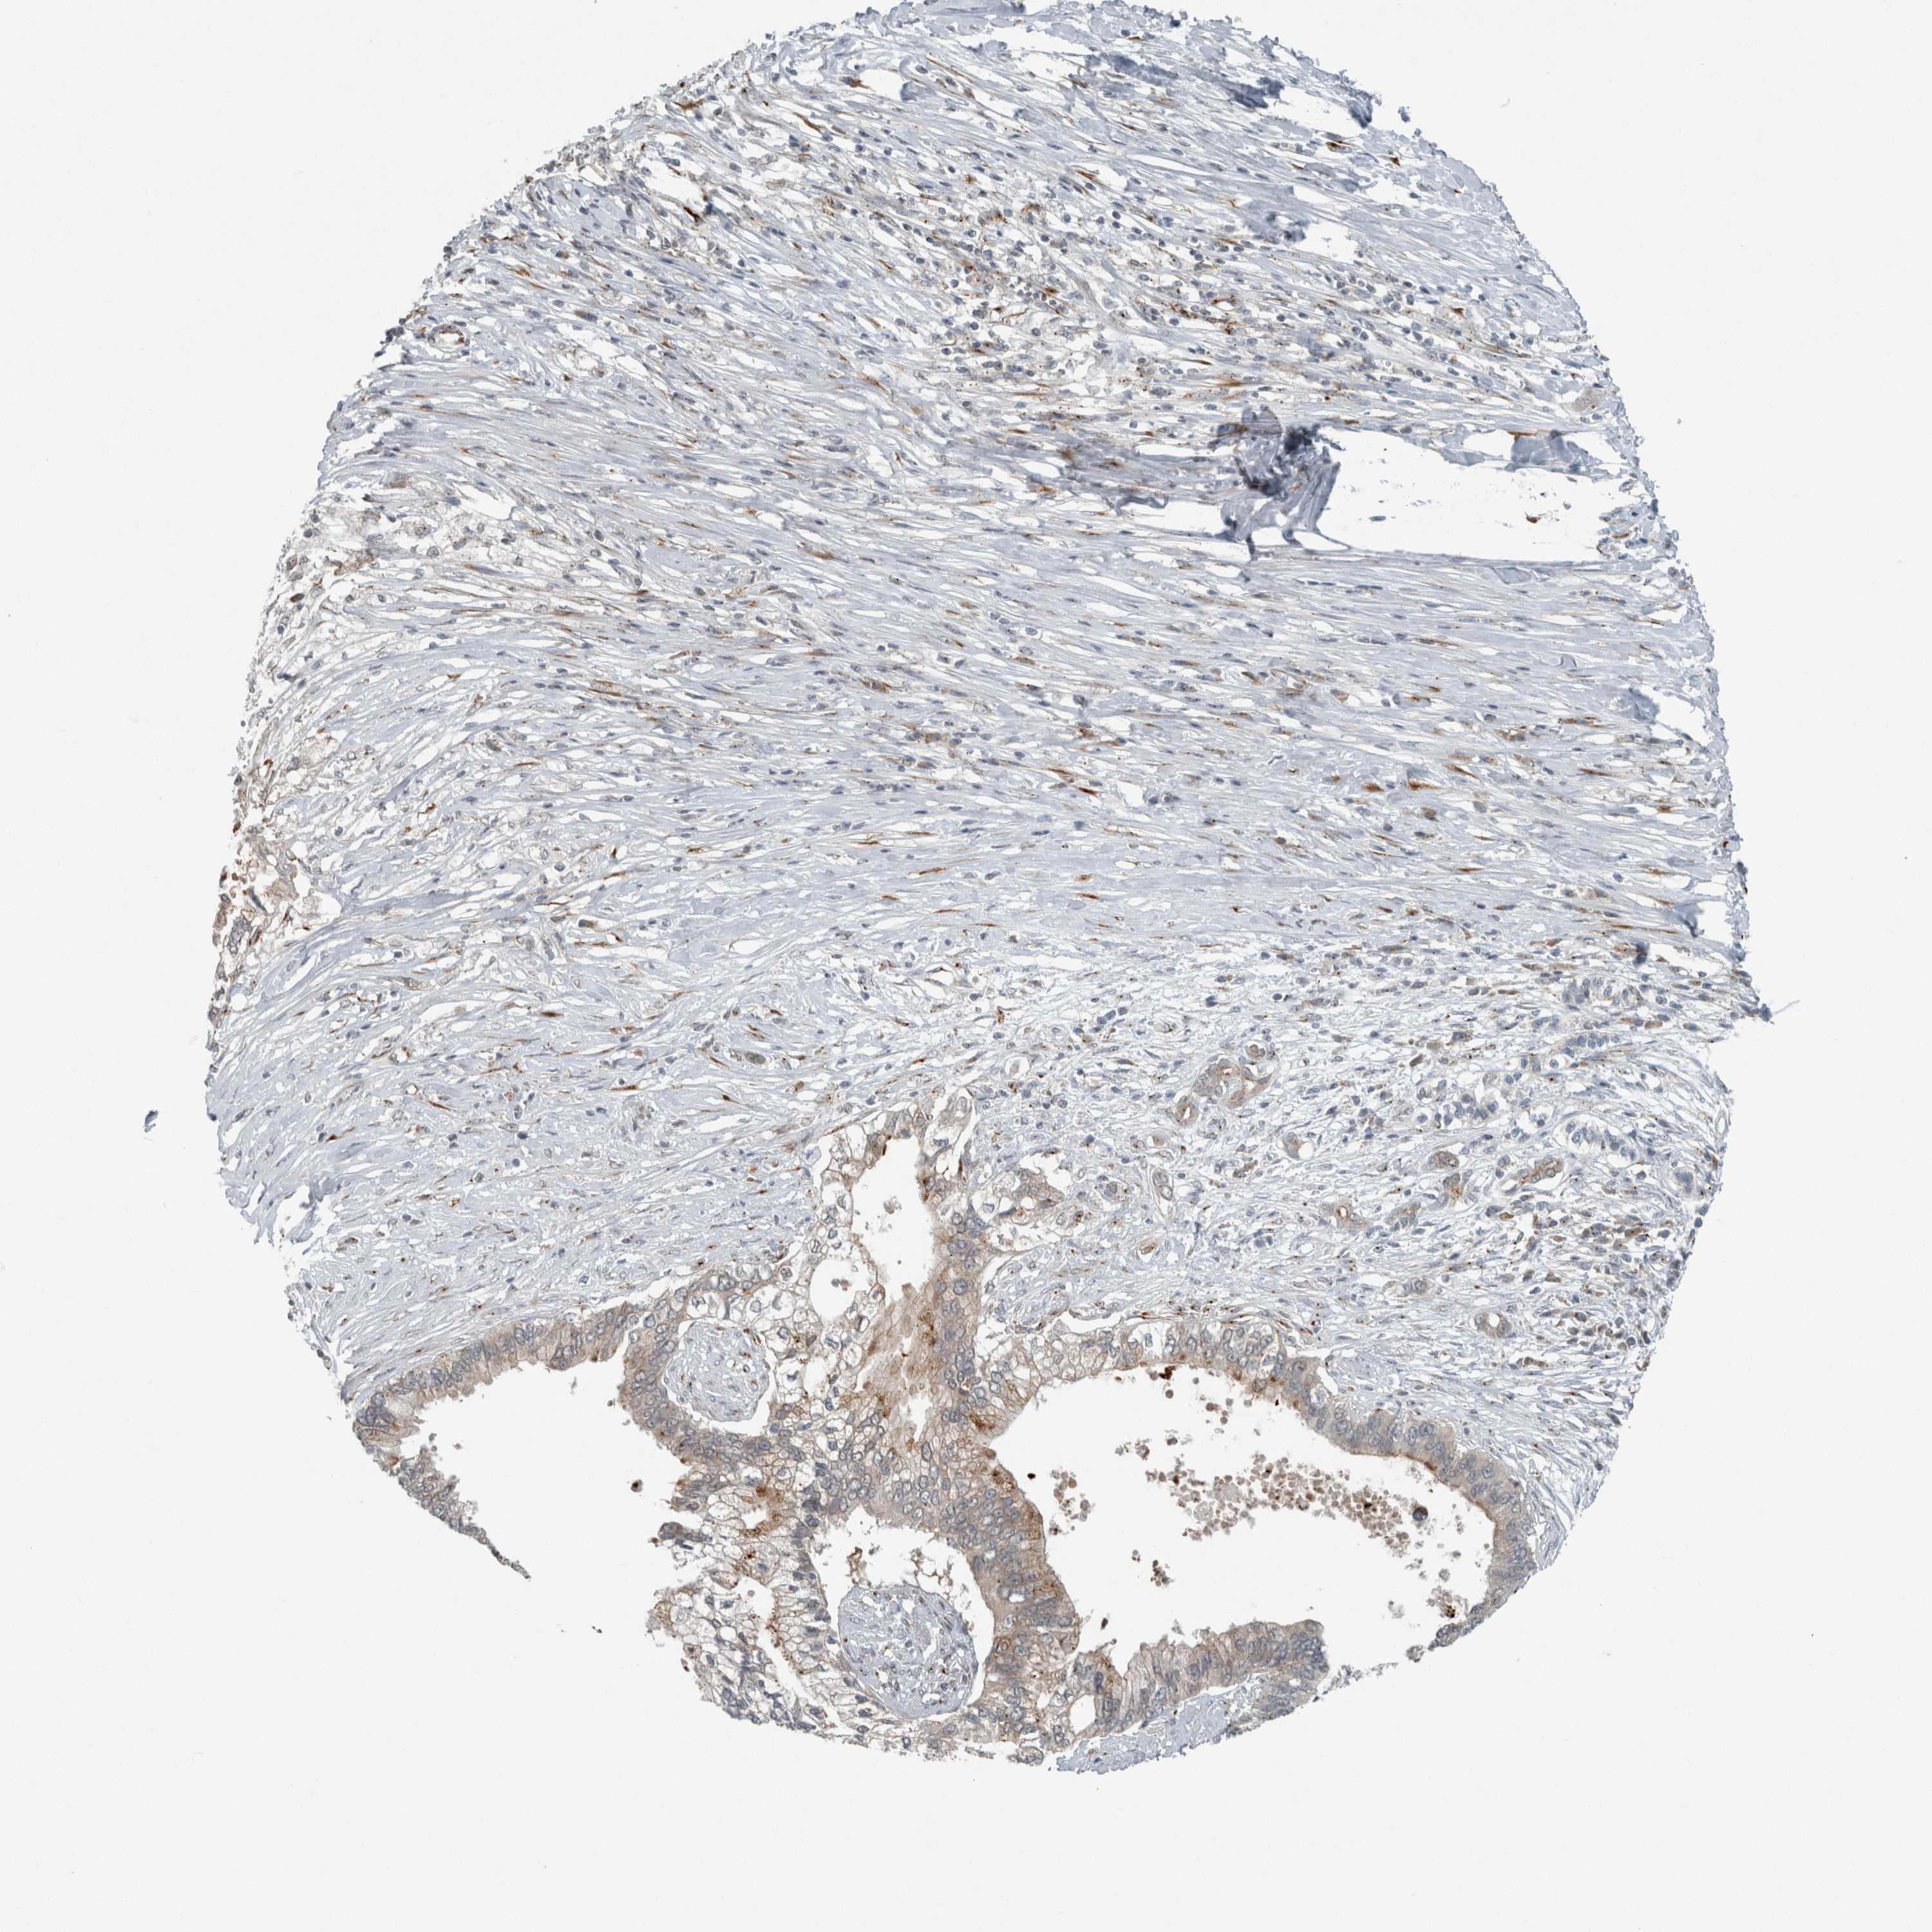

PANCREATIC CANCER - Protein expressioni

A mouse-over function shows sample information and annotation data. Click on an image to view it in a full screen mode. Samples can be filtered based on level of antibody staining by selecting one or several of the following categories: high, medium, low and not detected. The assay and annotation is described here.

Note that samples used for immunohistochemistry by the Human Protein Atlas do not correspond to samples in the TCGA dataset.

Antibody stainingi

Antibody staining in the annotated cell types in the current human tissue is reported as not detected, low, medium, or high, based on conventional immunohistochemistry profiling in selected tissues. This score is based on the combination of the staining intensity and fraction of stained cells.

Each image is clickable and will lead to virtual microscopy that enables deeper exploration of all samples and also displays staining intensity scores, fraction scores and subcellular localization as well as patient and tissue information for each sample.

Antibody HPA024602

Antibody HPA045020

Adenocarcinoma, NOS